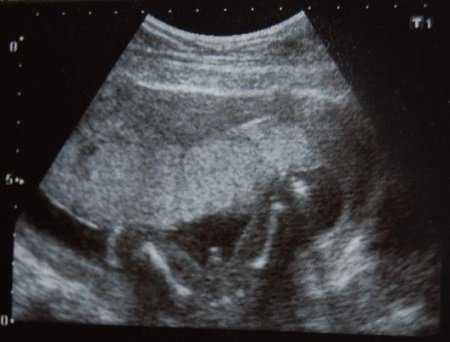

Выявить патологию может только врач во время осмотра. Отсутствие сердцебиения, несоответствие размера матки сроку — первые признаки замершей беременности на 17 неделе. Для подтверждения диагноза необходимо провести УЗИ.

Фото ребёнка на УЗИ

Предлагаем вам посмотреть варианты УЗИ на 17 неделе беременности.

УЗИ 17 недель

УЗИ беременность 17 недель

УЗИ при беременности 17 недель

Фото УЗИ 17 недель